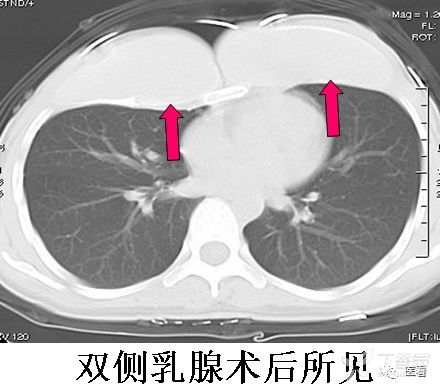

乳腺成形术或丰胸术后

尤其是患者隐瞒病情,或单侧手术时,需要注意鉴别。

辨识方法:充填物区无正常乳腺组织结构,呈密度均匀的无结构影(红箭)。注意双侧对照,或与正常人乳腺图像对照。